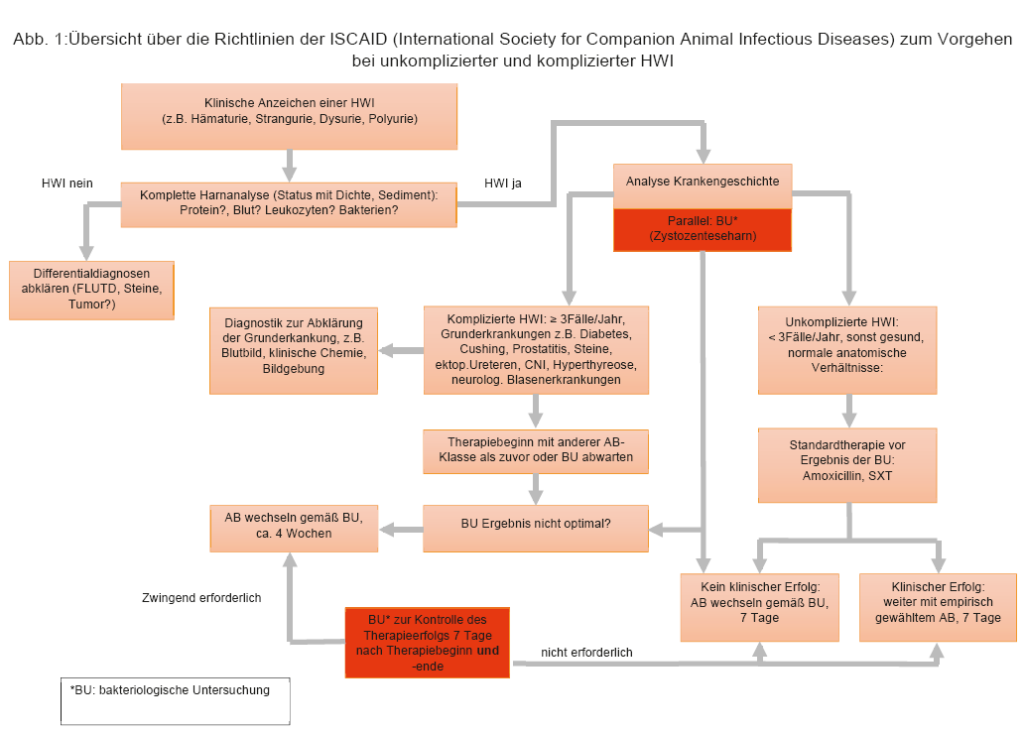

Die erreichbare Urinkonzentration eines Antibiotikums (AB) zur Therapie einer HWI sollte bei mindestens dem 4-fachen der minimalen Hemmkonzentration (MHK, s. LABOKLIN aktuell 1/2015) für dieses AB liegen. Dies stellt bei vielen AB-Klassen kein Problem dar, da sie über die aktive renale Ausscheidung eine zwischen 10- und 100-fache Konzentration im Urin im Vergleich zum Plasma erreichen. Dies bedeutet, dass im Einzelfall auch ein im Antibiogramm als intermediär (I) getestetes AB eingesetzt werden kann, sofern sich die im Labor ermittelten Werte auf erreichbare Plasmaspiegel beziehen. Dies wird meistens der Fall sein, da spezielle MHK-Werte für Urin bei Tieren nur in sehr geringem Umfang vorliegen. Zu den AB-Klassen, die sich besonders gut im Urin anreichern zählen u.a. Ampicillin, einfaches und potenziertes Amoxicillin, Chephalosporine, Quinolone, Gentamicin, und Sulfamethoxazol/Trimethoprim (SXT). Gentamicin ist aufgrund der Nebenwirkungen und Applikationsart grundsätzlich als letzte Wahl zu betrachten und nur einzusetzen, wenn laut Antibiogramm sonst nichts wirkt. Quinolone sollten auch nicht als erste Wahl eingesetzt werden, da sie die Selektion von multiresistenten Keimen erleichtern. 2011 wurden von einer Expertengruppe der International Society for Companion Animal Infectious Diseases (=ISCAID) (s. Abb1) Richtlinien zur Therapie von HWI erarbeitet. Diese Richtlinien geben für den praktizierenden Tierarzt klare und einfache Hilfestellungen für die Therapie von HWI unter Berücksichtigung bekannter Forschungsergebnisse und der dringenden Notwendigkeit Resistenzen zu vermeiden. Sie sind auch in der EU und im deutschsprachigen Raum anerkannt. Da es sich um internationale Richtlinien handelt, ist eine jeweilige Anpassung an die regionalen Gegebenheiten (lokale Resistenzmuster, Verfügbarkeit der vorgeschlagenen Antibiotika, gesetzliche Vorgaben) unumgänglich.

Es wird in unkomplizierte und komplizierte HWI unterschieden. Hierfür gibt es klare Einteilungskriterien und Therapievorschläge (s. Abb. 1). Bei der komplizierten HWI wird bei Wiederauftreten einer Infektion innerhalb von 6 Monaten noch zwischen Reinfektion und Rückfall unterschieden. Bei der Reinfektion kommt es nach zunächst erfolgreicher Therapie zur erneuten Infektion mit einem anderen Keim. Beim Rückfall handelt es sich um denselben Keim. Bei Nachweis der gleichen Bakterienart ist somit ein Vergleich der Antibiogramme hilfreich für die Unterscheidung. Beim Rückfall ist eine echte Elimination des Keims nicht gelungen und er erfolgt meist schneller, als die Reinfektion. Beim Rückfall sollte die Compliance des Besitzers, aber auch die richtige Auswahl des AB und der Dosis kritisch beleuchtet werden. Bei einer Reinfektion ist die Suche nach den prädisponierenden Faktoren entscheidend.

- Abb. 1: Übersicht über die Richtlinien der ISCAID (International Society for Companion Animal Infectious Diseases) zum Vorgehen bei unkomplizierter und komplizierter HWI